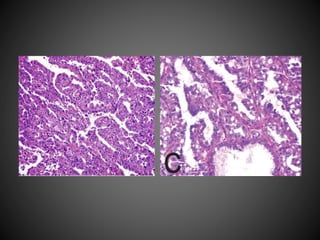

(A) Clear cell papillary renal cell carcinoma is a renal epithelial

neoplasm composed of low-grade clear epithelial cells arranged in

tubules and papillae with a predominantly linear nuclear alignment. (B)

The tumour cells have a characteristic diffuse CK7 positivity.

(A) Clear cellpapillary renal cell carcinoma is a renal epithelial neoplasm composed of low-grade clear epithelial cells arranged in tubules and papillae with a predominantly linear nuclear alignment. (B) The tumour cells have a characteristic diffuse CK7 positivity.